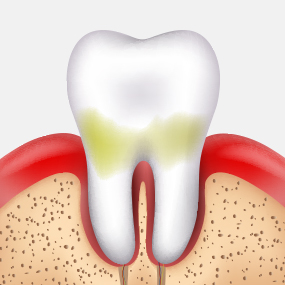

충치가 어느 정도 진행되었는지에 따라 치료 방법은 크게 달라질 수 있습니다. 서울하나치과는 정밀 진단을 통해 치아를 최대한 보존할 수 있는 치료법을 안내해드립니다.

CARIES TREATMENT

법랑질 안쪽에 있는 상아질까지 충치가 진행되어 뜨겁거나 차가운 음식을 먹으면 시린 증상이 나타납니다.

상아질 안쪽 신경까지

염증이 진행되어

극심한 통증으로

참기 어려운

정도가 됩니다.

치아 내부에 있는

조직이 괴사되고,

뿌리 주변의

염증으로 인하여

뼈가 점차 소실됩니다.